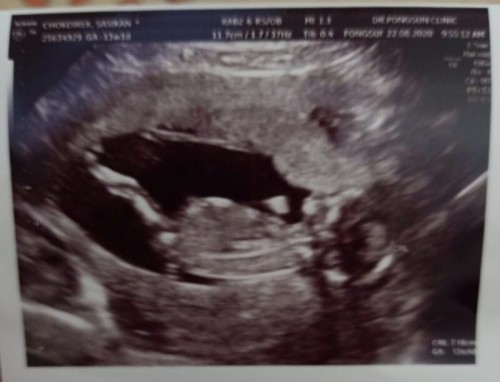

ได้ลูกชายครับบบ....13W1D...จ้า🥰🥰